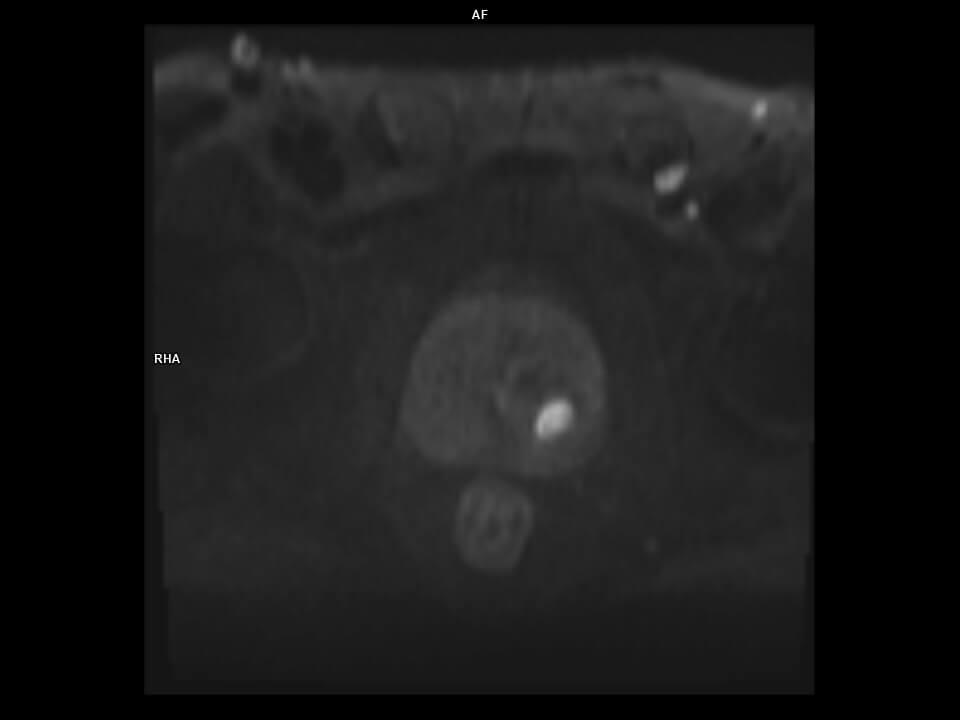

AXIAL EPI DWI_b1000-MAGNETOM Vida

AXIAL EPI DWI_b1000-MAGNETOM Vida/ULTRAFLEX 18 / SPINE 48/Scan Time-4:26/Aceleration-p2